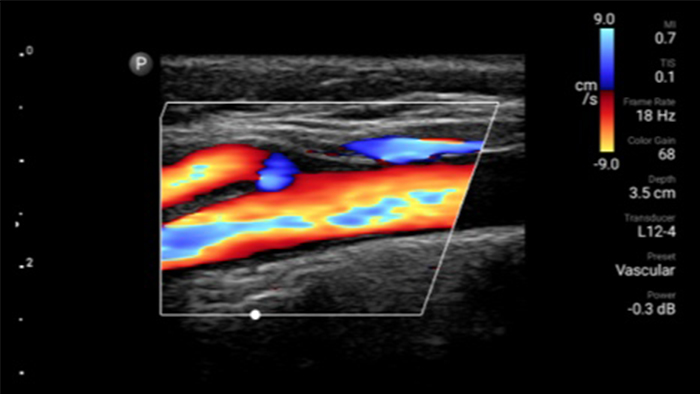

De Lumify draagbare echografieoplossing voor loco regionale anesthesiologie helpt u bij het visualiseren van de omliggende zenuwen, vaten, omliggende weefsels en naald-in situ tijdens de procedure.

Lumify helpt u de plaatsing van de naalden, de omringende zenuwen, vaten en fascia-vlakken duidelijk te visualiseren.

Lumify kan helpen de subtiele details van een beeld zichtbaar te maken en afwijkende weefselstructuren bloot te leggen vanuit verschillende hoeken. Hierdoor kunt u met vertrouwen realtime beslissingen nemen, van diagnose tot herstel.